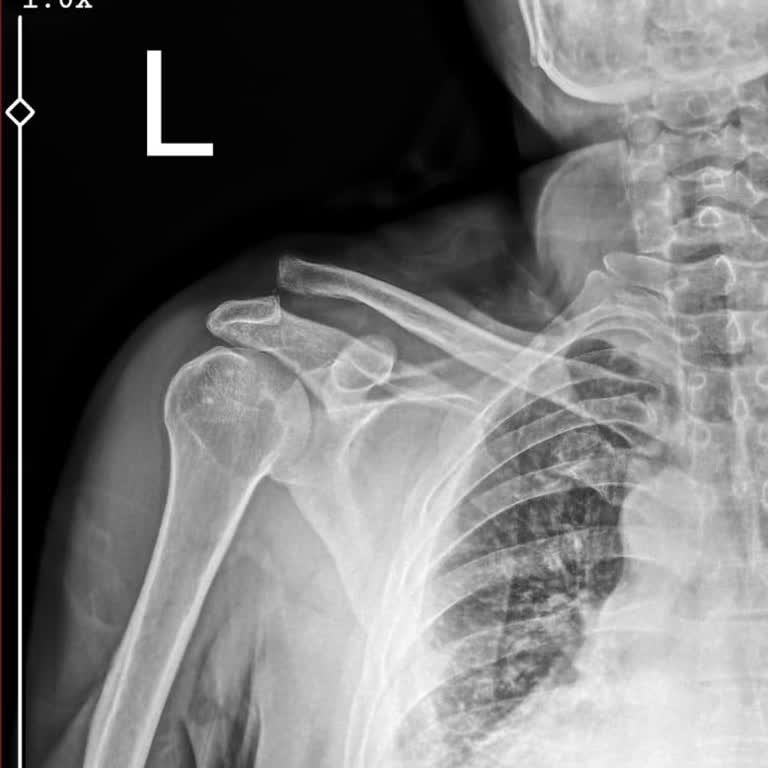

22.02.2025 tarihinde ayak baş parmağım çıktı. Acil serviste müdahalede edip ayağımı alçıya aldılar ve Ortopedi doktoruna yönlendirdiler. 24.02.2025 tarihinde Kocaeli Şehir Hastanesinde Doktor S**** A** G****'ye muayene oldum. Kendisi röntgen sonuçlarıma bakıp 2 hafta sonra tekrar kontrole gelmemi is...